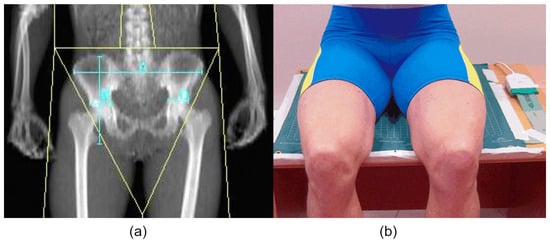

One to two weeks before testing in the laboratory, all participants took radiologic measurements using a DXA machine (DXA, Expert-XL, Lunar Corp., Madison, WI, USA), which is the most effective and accurate method for analyzing ischial tuberosities []. Objects made of plastic, metal, or other dense materials were removed before the participant was positioned on the DXA table. During the scan, participants lay supine and placed their hands at their sides as instructed by the manufacturer. Ischial tuberosity size and pelvis height and width were determined (Figure 2a, Table 2). Whole body mass (kg) was measured and body fat % was calculated (Table 2). Analyses were performed using the manufacturer’s software (Version 1.91). All scans and analyses were performed by the same experienced physician.

Figure 2. An example assessment of pelvis height and width and ischial tuberosity size of male road cyclists using a DXA machine (a) and cyclist position on the table during assessment of sitting distribution with a pressure mapping device (b).

Before and immediately following the cycling exercise, participants were seated on a table equipped with a pressure mapping device (ConforMat; Tekscan Inc., Boston, MA, USA) that measured 618.5 mm in width, 539.2 mm in length, and 0.762 mm in height (Figure 2b).